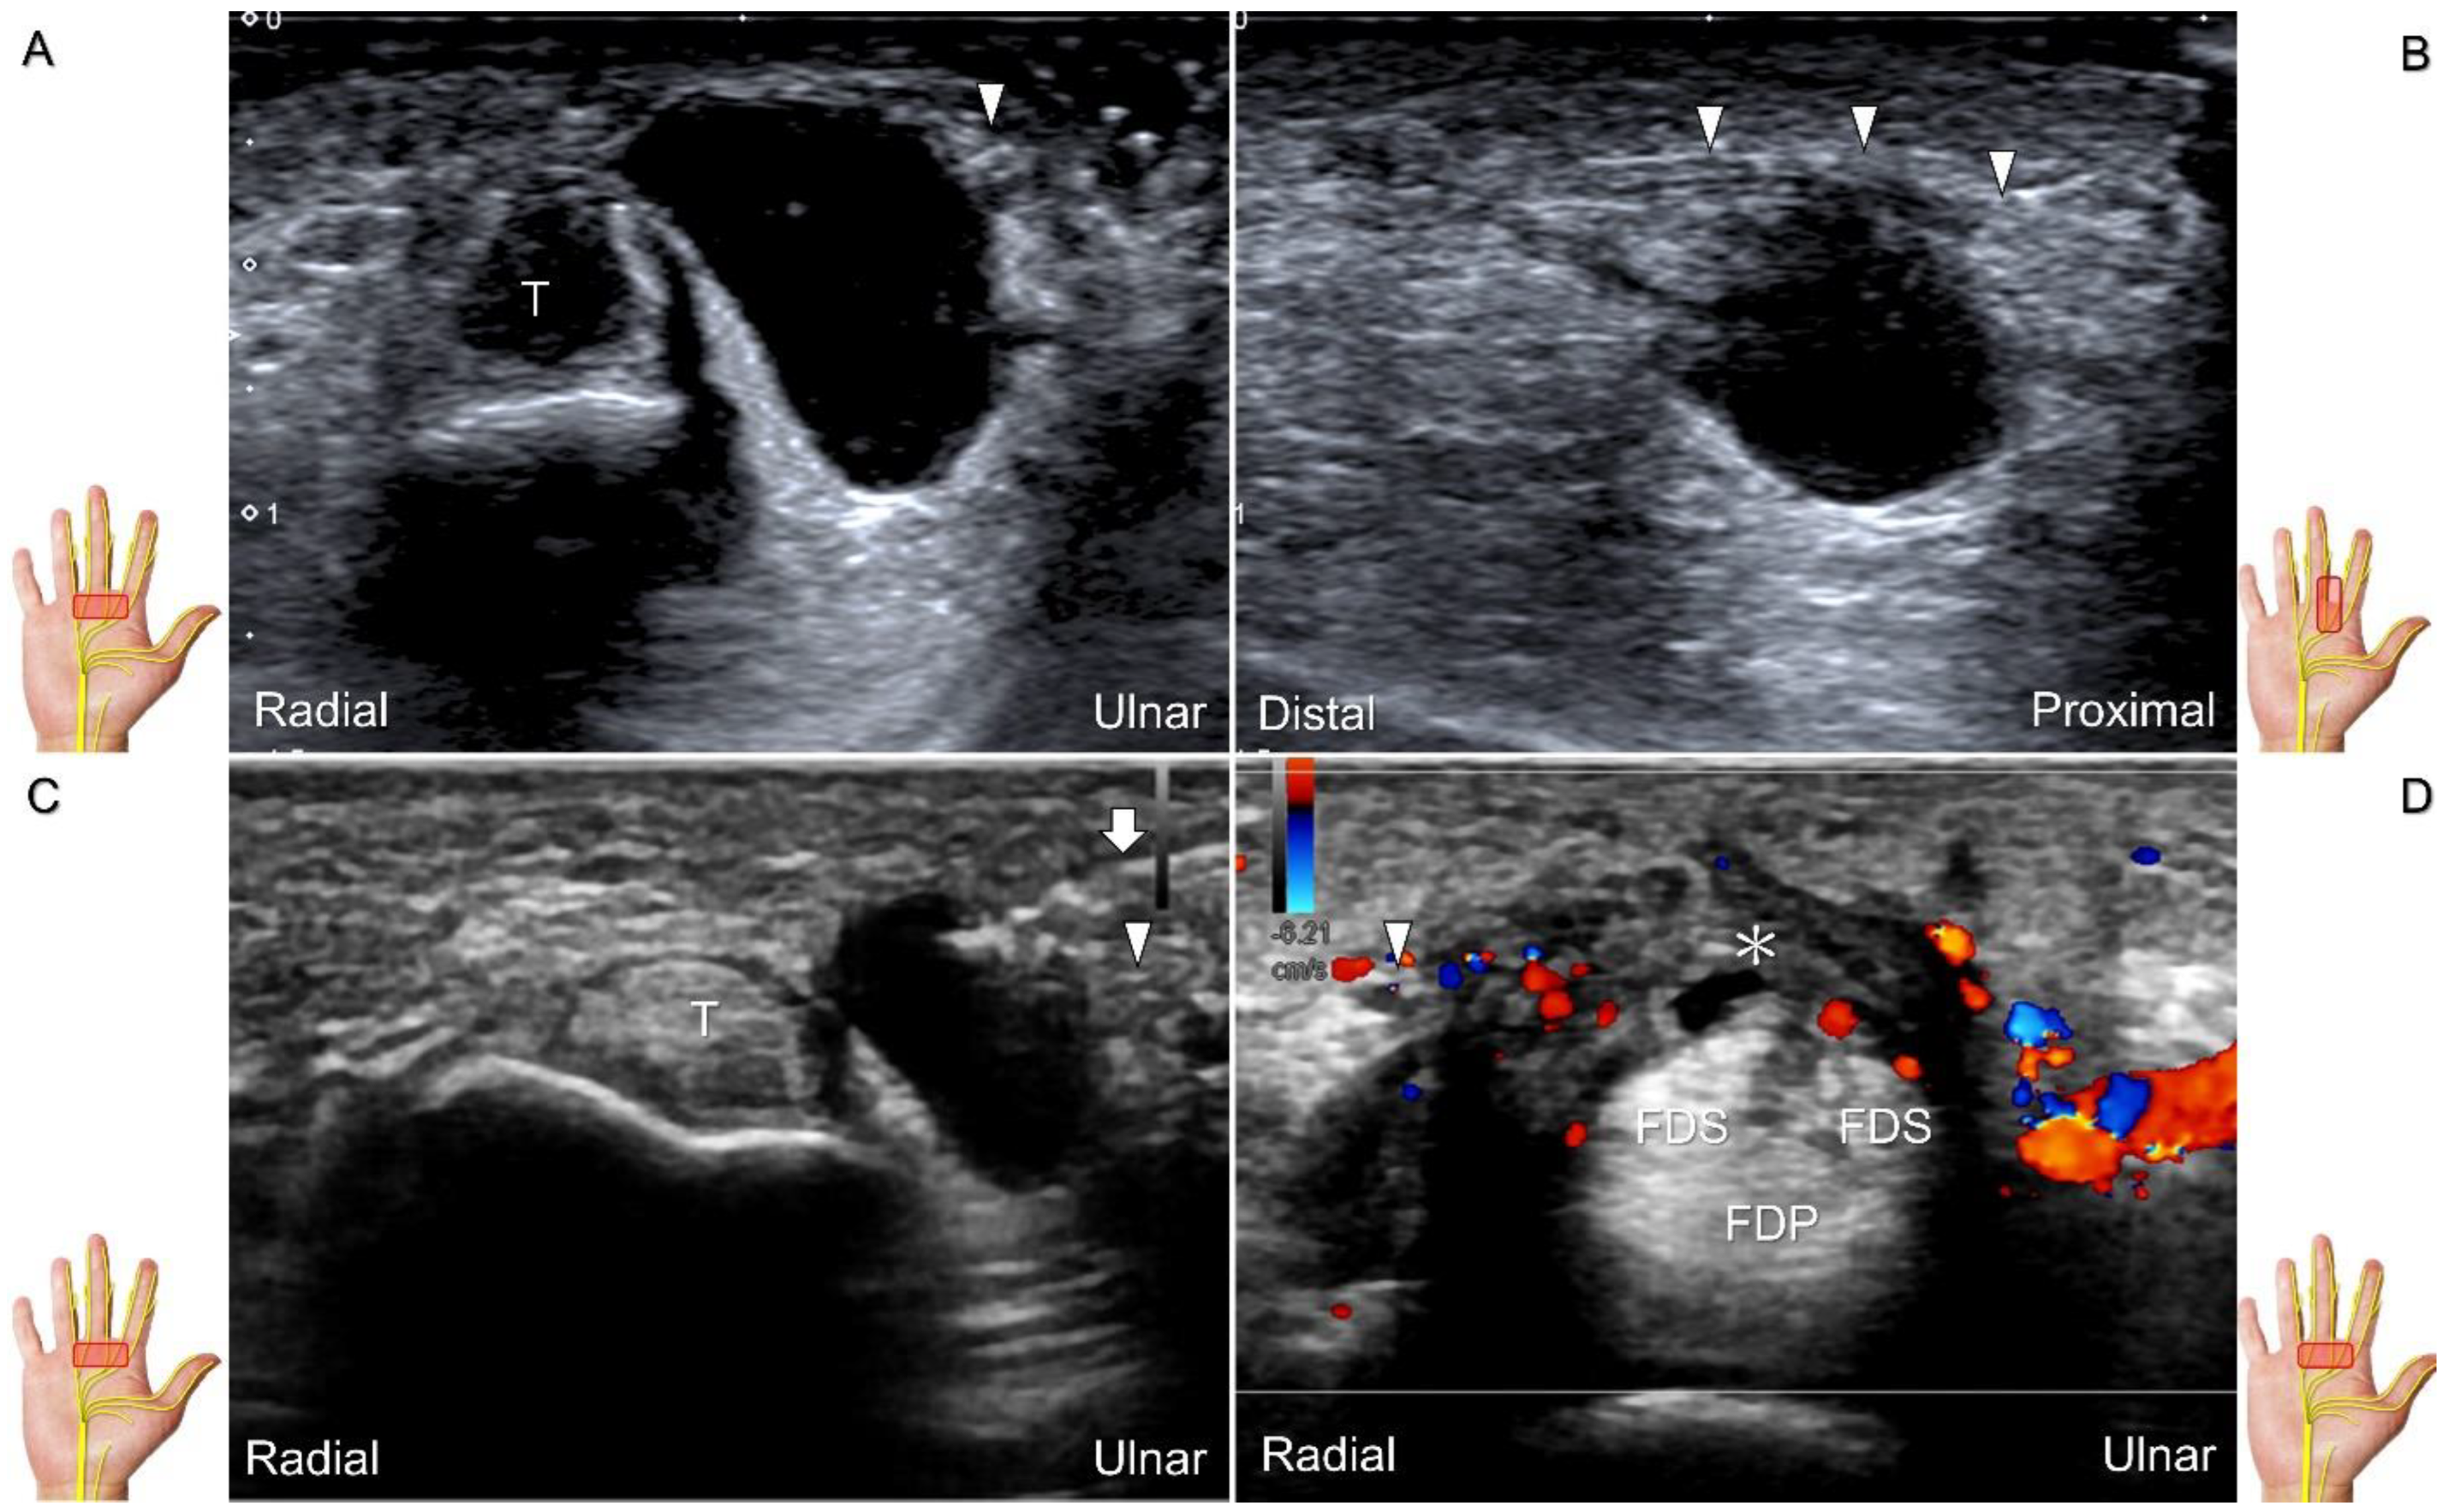

Scanning Technique

The transducer is placed on the mid-palm in the axial plane (Figure 28A). The palmar common digital nerves course beside the flexor digitorum profundus/superficialis tendons with the palmar common digital artery, and they are superficial to the palmar interosseous muscles (Figure 28B). Moving the transducer more distally, the palmar proper digital nerves can be identified alongside all phalanges (Figure 28C,D).

Clinical Implication

Direct injury of the palmar common digital nerve can occur due to various reasons such as trauma, contusion, or iatrogenically during tendon injection. Nerve entrapment caused by space-occupying lesions such as fractures, ganglia (Figure 29A–C), annular ligament tears (Figure 29D), tenosynovitis, foreign bodies, fibroma (Figure 30A,B), or hemangioma (Figure 30C–E) is also likely.

Chronic irritation may lead to the formation of a neuroma, which can occasionally be detected through US imaging (Figure 31). Using the in-plane approach in short-axis view (Figure 32, Video S4), hydrodissection of the entrapped nerves can be performed after identifying the palmar common digital artery and flexor digitorum superficialis/profundus tendons.

Figure 28. Sonographic imaging of the palmar common digital nerves in short-axis (A) and long-axis (B) views. Palmar proper digital nerves from the base (C) to the head of the proximal phalanx (D). White arrowheads: palmar common digital nerves; black arrowheads: palmar proper digital nerves. T: flexor tendon; L: lumbricalis muscle; PIO: palmar interosseous muscle; FDS: flexor digitorum superficialis tendon; FDP: flexor digitorum profundus tendon; A: artery; VP: volar plate; PP: proximal phalanx; PPh: head of the proximal phalanx.

Figure 29. Ultrasound images demonstrate the entrapment of the palmar common digital nerve due to a ganglion seen in short-axis (A) and long-axis (B) views. Ultrasound-guided aspiration (C). Nerve entrapment due to annular ligament tear (asterisk) following an iatrogenic injury (D). Arrowheads: palmar common digital nerve; Arrow: needle; T: flexor tendon; FDS: flexor digitorum superficialis tendon; FDP: flexor digitorum profundus tendon.